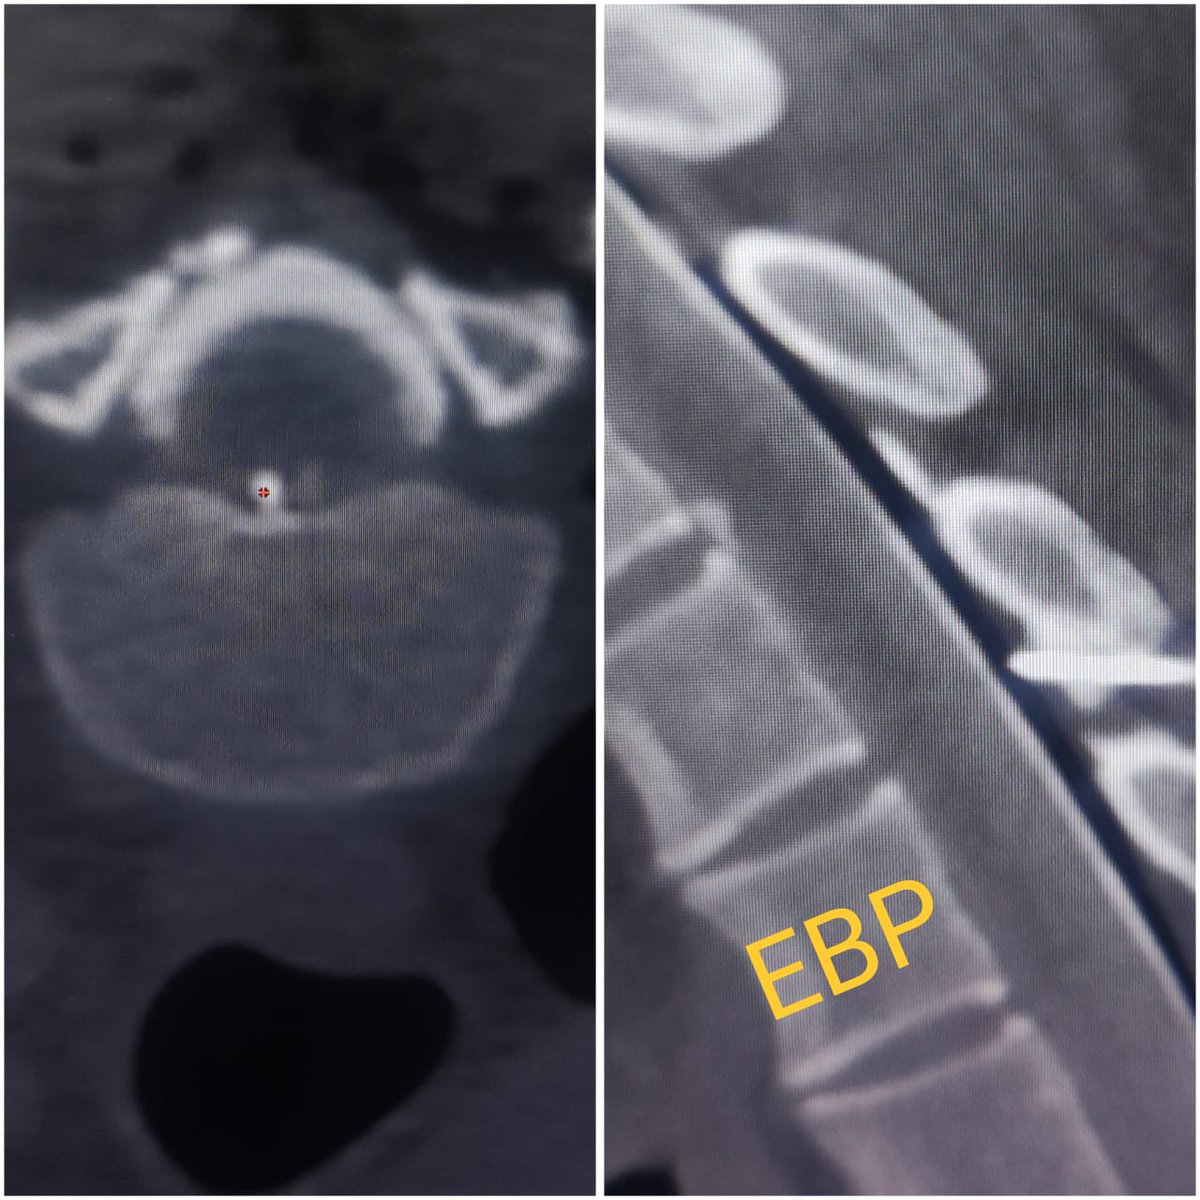

Symptomatic Type 1A spinal CSF leak due to bony spur. SIH score 9/9, treated with EBP and hopefully it will offer some long term benefits! #sih #SpinalCSFleak #headache #EBP @spinalCSFleak @The_ASSR @SpinalCSFCanada @CarolinaIten

SharathKumarGG7's tweet image. Symptomatic Type 1A spinal CSF leak due to bony spur. SIH score 9/9, treated with EBP and hopefully it will offer some long term benefits! #sih #SpinalCSFleak #headache #EBP @spinalCSFleak @The_ASSR @SpinalCSFCanada @CarolinaIten